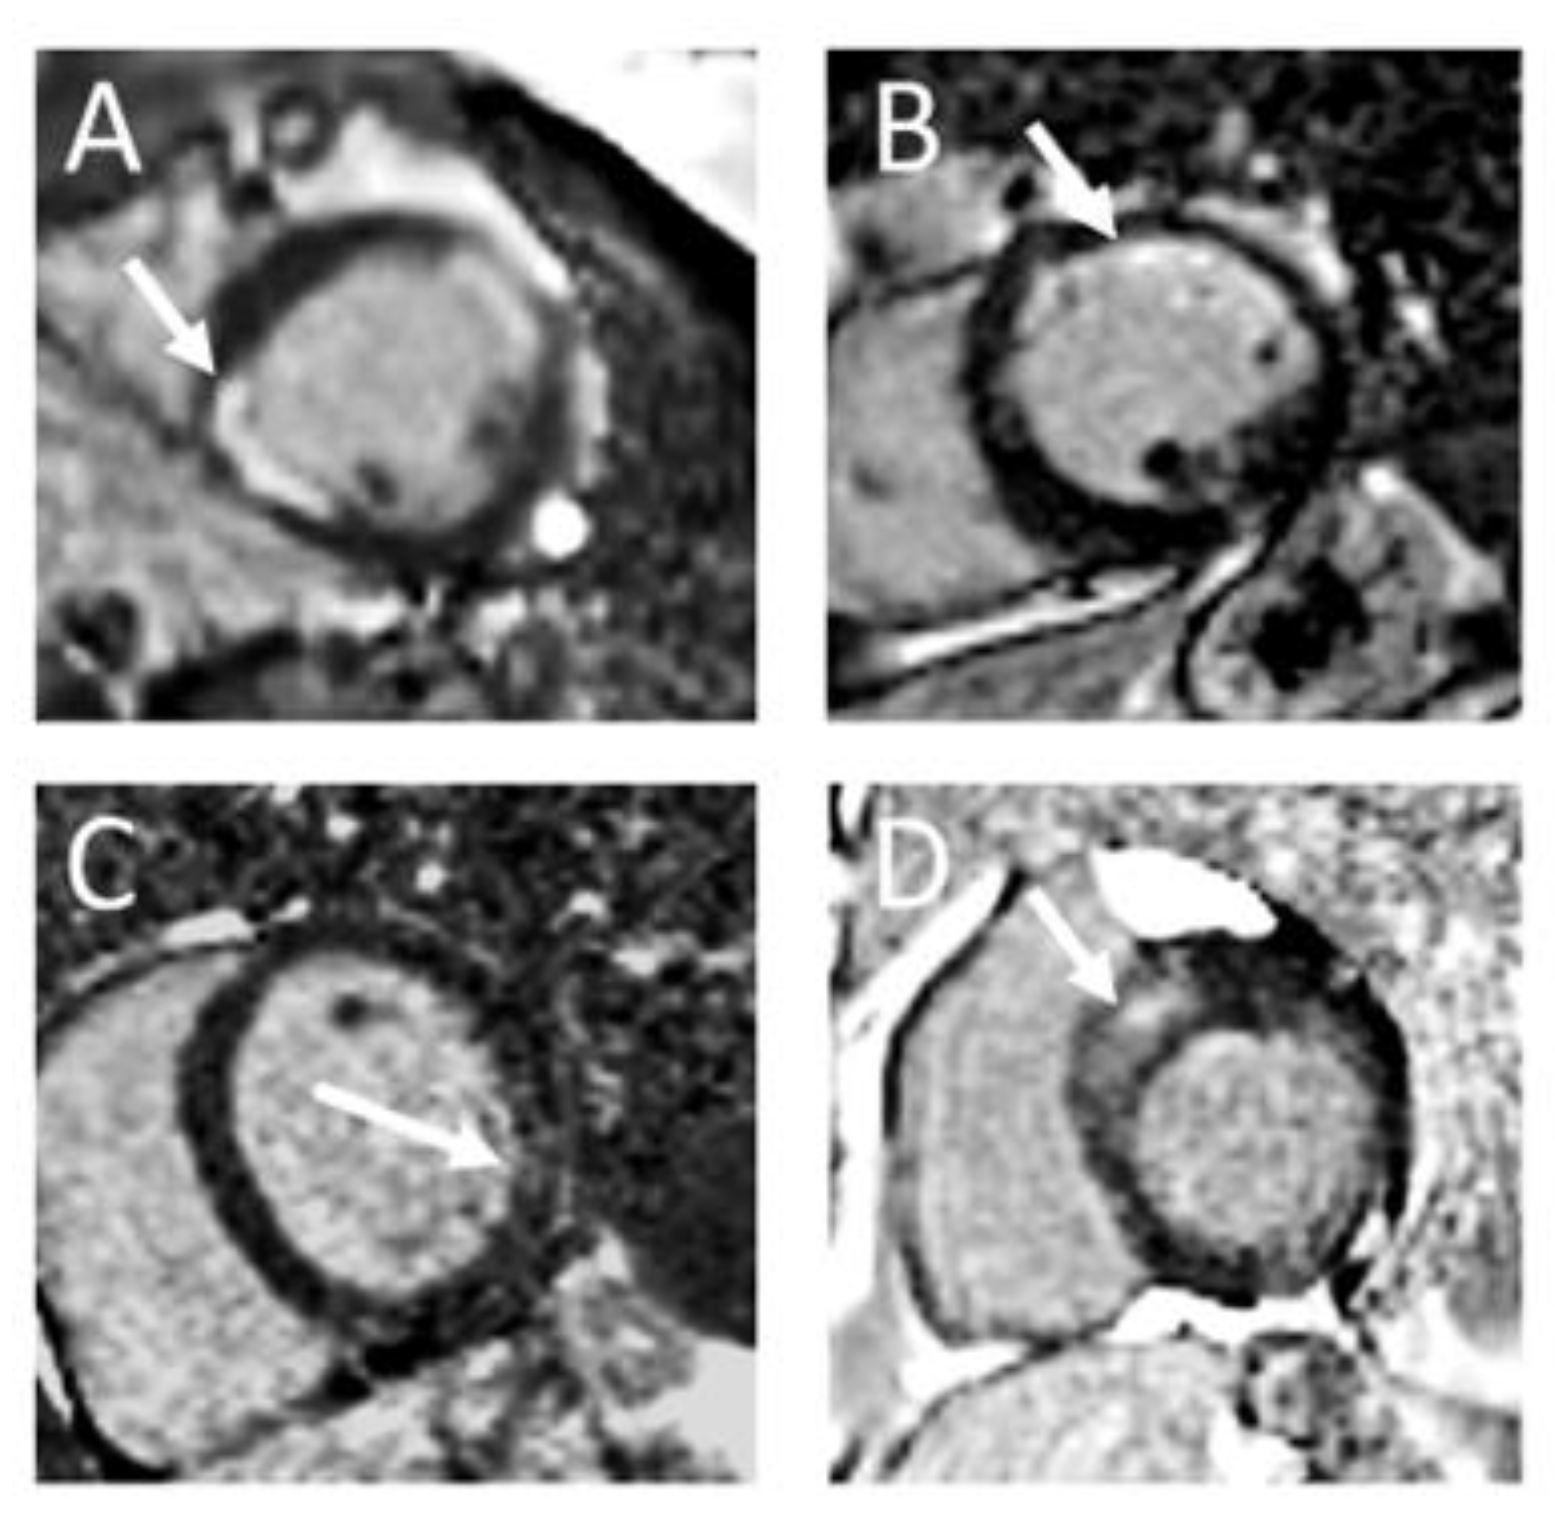

- Bietenbeck, M.; Meier, C.; Korthals, D.; Theofanidou, M.; Stalling, P.; Dittmann, S.; Schulze-Bahr, E.; Eckardt, L.; Yilmaz, A. Possible Causes and Clinical Relevance of a “Ring-Like” Late Gadolinium Enhancement Pattern. JACC Cardiovasc. Imaging 2023, 17, 104–106. [Google Scholar] [CrossRef] [PubMed]